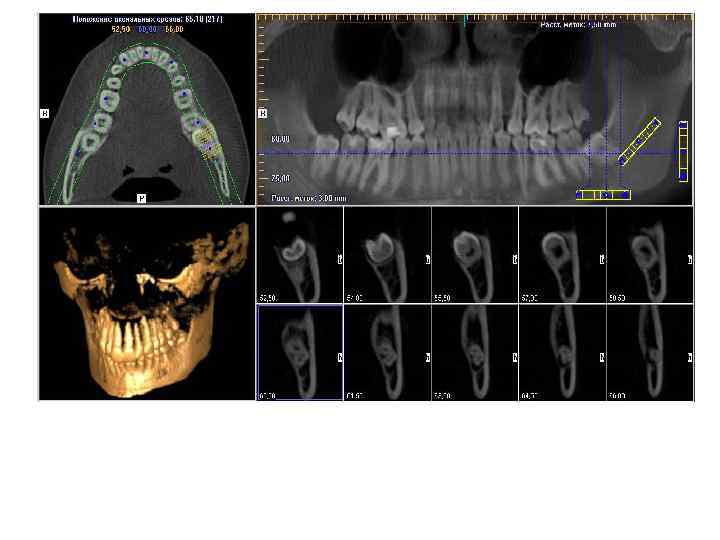

Конусно лучевая компьютерная томография — полуретенция зубов 1. 8, 2. 8, 3. 8, 4. 8, дистопия зубов 2. 8, 4. 8

Конусно лучевая компьютерная томография — полуретенция, дистопия зуба 4. 8

Конусно лучевая компьютерная томография — ретенция, дистопия зуба 2. 8

Конусно лучевая компьютерная томография — инклюзия зуба 3. 3